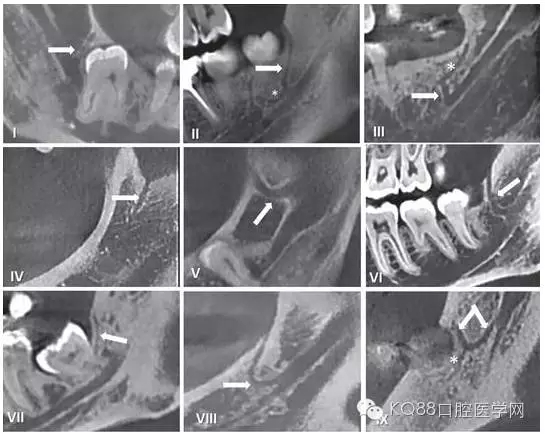

在臨床工作中,個體解剖差異導致像磨牙后管這類的神經(jīng)分叉及神經(jīng)走行的變化,術前只能通過放射方法檢測。但使用口腔曲面斷層片之類的常規(guī)二維影像學照片是難以檢查到的。隨著現(xiàn)代醫(yī)學影像技術的發(fā)展,出現(xiàn)了計算機斷層掃描(CT)和錐束CT(CBCT),其在口腔醫(yī)學領域的成功運用使得磨牙后管的術前影像評估成為可能。精確的捕捉到下頜磨牙后管的解剖走行,需要高分辨率的成像設備并保證攝像期間患者沒有晃動。下面我們將用幾張CBCT影像圖片為大家圖示說明。

圖五 使用CBCT拍攝到的不同走行的下頜后管

通過對磨牙后三角(RMT),磨牙后孔(RMF)和磨牙后管(RMC)解剖學結構及其臨床走行的認識,將會幫助我們在臨床工作中,進一步減少磨牙后區(qū)操作所造成的意外損傷。